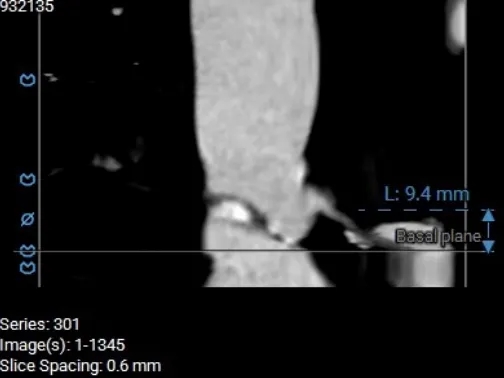

术前CT分析

主动脉根部测量

Annulus 20.7mm

LVOT 21.3mm

钙化积分 612

SOV

27.9*26.8*27.1mm

STJ 22.6mm

AAO 28.8mm

瓣上结构测量

瓣上2mm

20.5mm

瓣上4mm

19.9mm

瓣上6mm

20.7mm

瓣上8mm

20.2mm

瓣上10mm

20.8mm

瓣上12mm

21.9mm